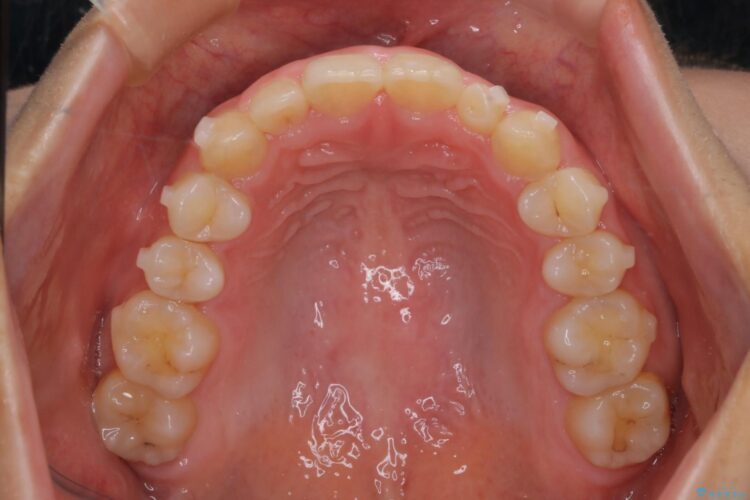

軽度のガタつきだあったのと、かみ合わせがやや深かったため、インビザラインで治療を行うこととしました。

IPR(歯と歯の間を削る処置)と歯列拡大をすることでガタつきをとります。

前歯のガタつきを改善するのに時間がかかりましたが、ガタつきもかみ合わせも綺麗になりました。

患者様の希望で、矯正終了後にホワイトニングも行い歯の色味も自然な白さになりました。